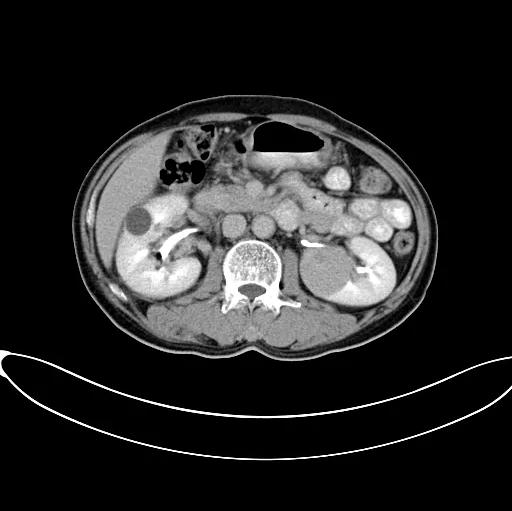

2017年9月安圖叔叔開啟新治療之路,入院檢查發(fā)現(xiàn)安圖叔叔右腎透明細胞癌T3NxM1IV期、左腎癌、縱隔淋巴結轉移瘤。為緩解安圖叔叔腰疼的狀況,9月21日進行介入治療。經(jīng)復大專家認真探討后,考慮到安圖叔叔身體精神狀態(tài)良好,可進行冷凍消融術。經(jīng)專家解說和安慰后,安圖一家懸著心終于放下了。

2017年9月29日,從CT影像看到右腎情況更為嚴重。為減緩腫瘤增長的速度,專家進行商議后,最終決定由牛立志教授主刀為安圖叔叔進行了右腎腫瘤冷凍消融術。手術開始后,牛立志教授在CT和超聲引導下,同時使用兩根冷凍針固定病灶,精準滅活腫瘤;術后很成功無不良反應。術后一周進行第二次雙腎腫瘤冷凍消融術。安圖叔叔兒子笑道:“當時真的很緊張,醫(yī)生勸慰我無須擔心,都交給他們,我們都很清楚知道父親的病情,真的很感謝也很慶幸我父親遇到復大的醫(yī)護人員,免受開刀之痛。住院期間醫(yī)護人員很盡心盡力的照顧父親,手術的成功離不開他們的辛勞付出!